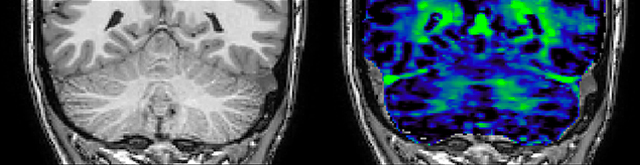

of limiting MWI to the brain, even without the cerebellum, we can now spend about the same amount of time and scan the whole brain and the cervical spinal cord, which is a huge boost for us.” Dr. Rauscher says, “For MWI we perform 3D T2 with 32 or more echoes. This used to take a long time, but with Compressed SENSE we can decrease this to ten minutes for the whole head. Because of the large field of view (FOV) on the readout direction, we even get information from the brainstem, which we previously missed when we were using the GRASE approach. Having the whole head scan is nice because it has spatial resolution, orientation and FOV that are comparable to the standard 3D clinical MS scans, including the FLAIR and 3D T2, and a 3D T1 for brain volume.”

T1 - Weighted, Myelin Water Fraction Superimposed

Spinal cord coverage

Smaller, more isotropic voxels

Excellent detail in quantitative maps

Images courtesy of Adam Dvorak, Department of Physics and Astronomy, University of British Columbia